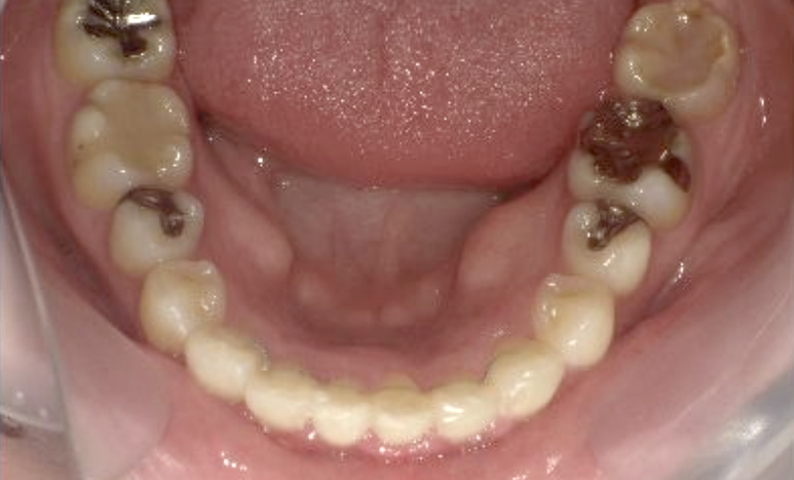

症例_004 下顎だけの部分矯正

治療期間:10ヶ月金額:30万円+税女性前歯のガタガタ下の前歯だけ

| Before | After |